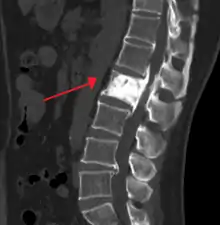

Paget's disease of bone

Paget's disease of bone (commonly known as Paget's disease or, historically, osteitis deformans) is a condition involving cellular remodeling and deformity of one or more bones. The affected bones show signs of dysregulated bone remodeling at the microscopic level, specifically excessive bone breakdown and subsequent disorganized new bone formation.[1] These structural changes cause the bone to weaken, which may result in deformity, pain, fracture or arthritis of associated joints.[1]

Initially, there is a marked increase in the rate of bone resorption in localized areas, caused by large and numerous osteoclasts. These localized areas of pathological destruction of bone tissue (osteolysis) are seen radiologically as an advancing lytic wedge in long bones or the skull. When this occurs in the skull, it is called osteoporosis circumscripta. The osteolysis is followed by a compensatory increase in bone formation induced by the bone-forming cells, called osteoblasts, that are recruited to the area. This is associated with accelerated deposition of lamellar bone in a disorganized fashion. This intense cellular activity produces a chaotic picture of trabecular bone ("mosaic" pattern), rather than the normal linear lamellar pattern. The resorbed bone is replaced and the marrow spaces are filled by an excess of fibrous connective tissue with a marked increase in blood vessels, causing the bone to become hypervascular. The bone hypercellularity may then diminish, leaving a dense "pagetic bone," also known as burned-out Paget's disease. A later phase of the disease is characterized by the replacement of normal bone marrow with highly vascular fibrous tissue.[25]